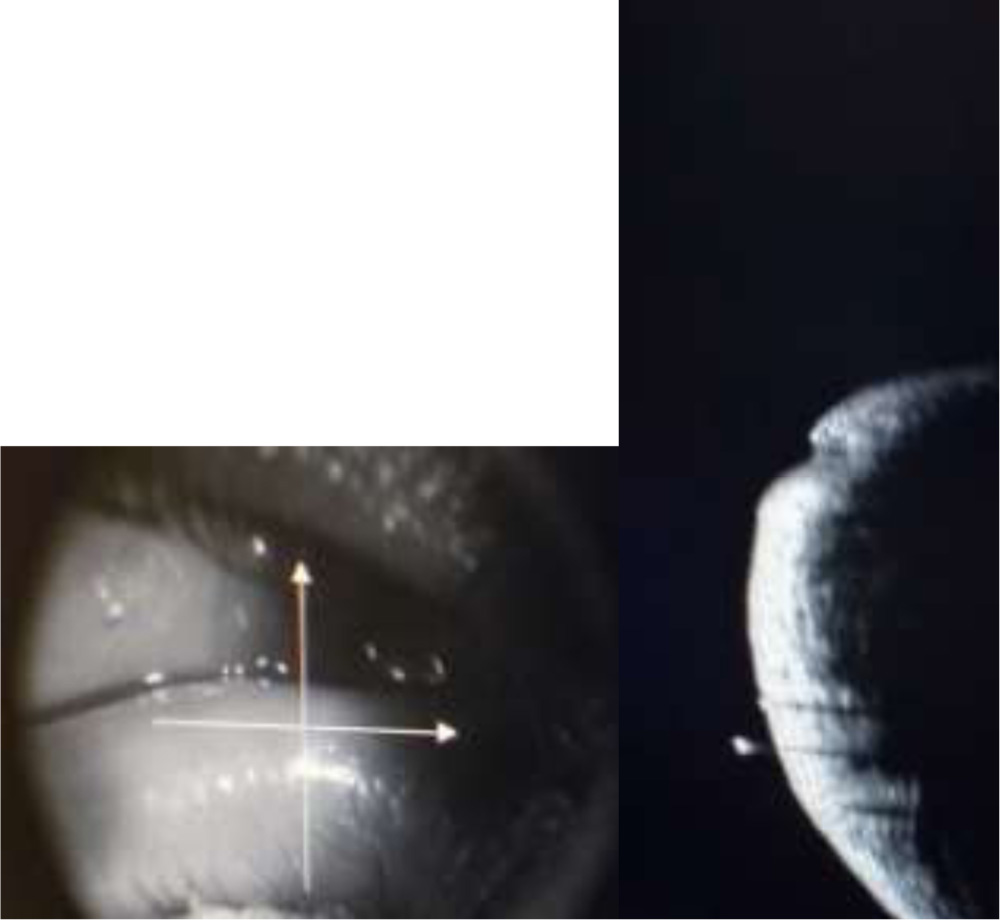

Subjects were positioned at the ASOCT machine and lower lid was gently everted to align the punctum against the light source . Additional illumination was provided by two external cables with red LED lights. A cross line scan was chosen for imaging and 6mm×6mm cross lines were positioned at the punctum.(Fig 1). Three sequential images were taken and the image with maximum extent and depth of visible punctum and vertical canaliculus was selected for measurements.

Fig 1. Horizontal and vetical cross lines centered on the punctum. Horizontal cross line measures the width of the punctum while vertical cross line measures the depth of the punctum.